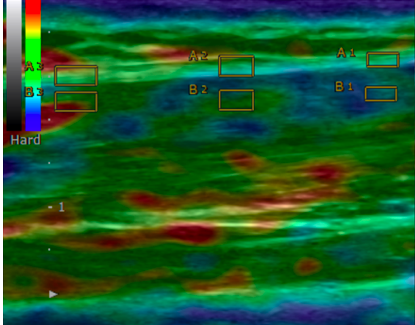

A key component of this evaluation is the use of ultrasound elastography, a specialized imaging technique that measures both the thickness and stiffness of deep fascia. In hypermobile spectrum disorders, excess extracellular matrix deposition leads to an increase in deep fascia thickness, while the stiffness of the fascia, as assessed by elastography, is often lower than normal. This reduction in stiffness reflects underlying connective tissue changes that contribute to the clinical manifestations of hEDS. The integration of these advanced diagnostic tools aids in a more accurate diagnosis and provides insights into the structural abnormalities of the fascia and tendons, facilitating targeted therapeutic strategies.

SCM Fascia Thickness (normal < 1.5mm) SCM Strain index (normal SI approximately 2.1)